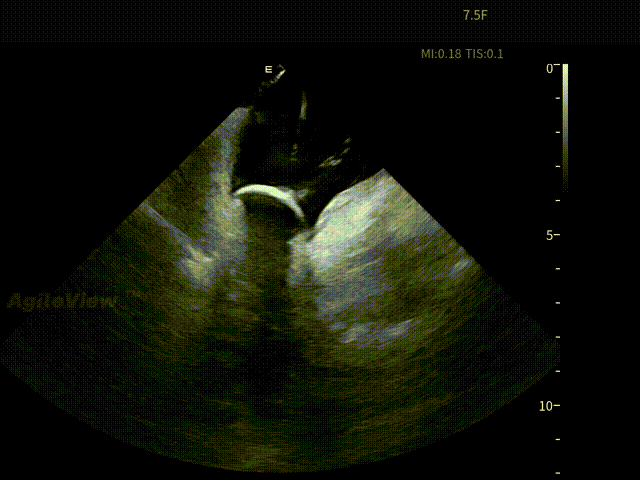

术中,基于AgileView™ 7.5Fr全球最细直径ICE导管的产品优势,周纬教授选择将ICE送入左房,以便更好地进行冷冻球囊的贴靠与位置的判断,在AgileView™ ICE实时影像的指导下, Arctic Front Advance Pro冷冻球囊导管消融导管安全进入左心房,先后完成双侧肺静脉隔离及顶部线隔离, ICE下可见导管贴靠良好,整个消融过程顺利,消融时间仅约25分钟,得益于超声设备清晰的成像质量,在顶部线隔离的时候可借助多普勒模式清晰的观察到球囊与组织的贴靠程度。 整个手术流程在ICE影像的指引下顺利完成,术中患者耐受良好,生命体征保持平稳。

球囊充气

球囊复温后“Blood Bubble”